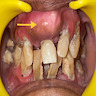

Clinical images

- Larger / solitary lesions present as painless swelling that causes jaw expansion, facial asymmetry, tooth divergence (Heliyon 2021;7:e07594)

- Grows slowly but can reach a considerable size if left untreated (Head Neck Pathol 2020;14:70)

- Extension to the nasal septum, orbital floor and infraorbital foramen can be seen in larger lesions; rarely associated with the destruction of extraosseous soft tissue components (Heliyon 2021;7:e07594)